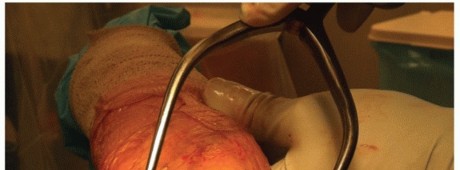

Anterior shoulder can be approached through two different incisions. Anterior incision

A 10- to 15-cm incision along the deltopectoral interval (FIG 1A)

Incision begins just above the coracoid process and progresses toward the deltoid tuberosity.

Axillary incision

Vertical incision 8 to 10 cm long (FIG 1B)

Incision begins inferior to the tip of the coracoid and progresses toward the anterior axillary fold.

FIG 1 • A. Deltopectoral incision. B. Axillary incision beginning inferior to the tip of the coracoid and progressing toward the anterior axillary fold. C. In this dissection, the subscapularis tendon is being tagged at the superior border of the rotator interval.